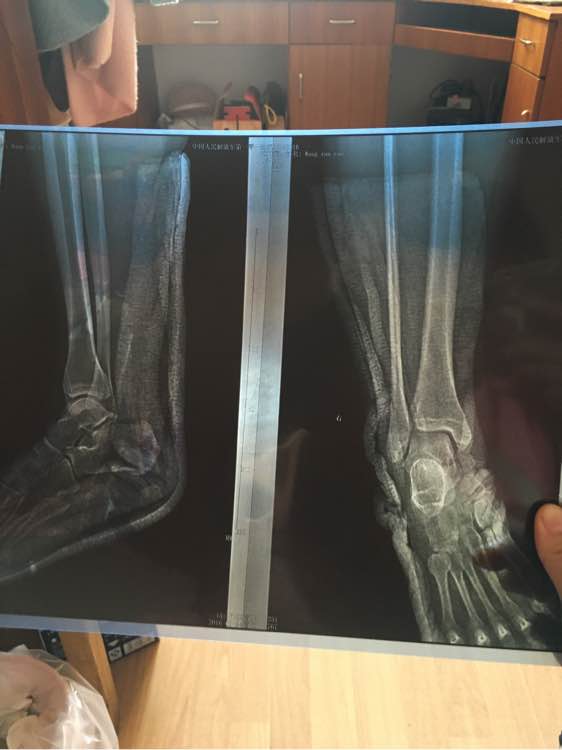

这是我骨折后一个星期拍的片子

小的是一个星期拍的,大的是一个月拍的

还有最后一张,刚骨折拍的,我感觉从刚骨折到一个月复查,没多大问题,到一个月骨缝越看做清楚了怎么回事

回复 多多是小坏蛋 :楼下还有张图,是刚骨折时候拍的,片子要比一个星期拍的还要小一点

回复 多多是小坏蛋 :RT机质量问题吧,最后一张都看不到哪里骨折

回复 qwvb6 :最后一张是我刚骨折拍的片子,怪不得那家医院最便宜,,两次拍的片都是去的一家医院

回复 多多是小坏蛋 :你这照片,脚的角度不一致,尺寸大小不同,大的就清楚点,小而模糊,